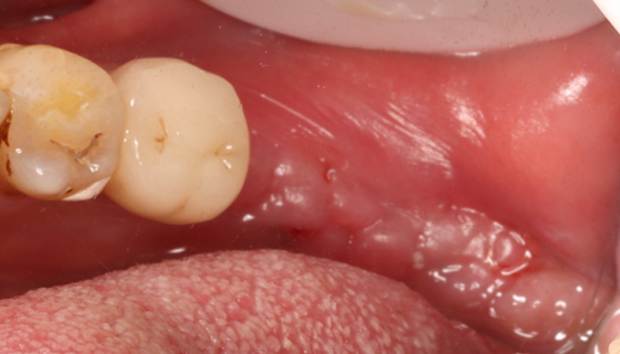

Pre-extraction images